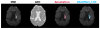

We provide a DL based tool for detection and segmentation of ischemic acute/sub-acute strokes, trained and tested in 2,628 brain MRIs. Using the original DWI as input, this fully automated system outputs 3D digital infarct mask, volume, and the feature vectors of regions affected by the infarct in two parcellation schemes: structural anatomy and arterial territories. The method is fast (the lesion inference takes 20~30 seconds in CPU; the total processing, including image registration and generation of reports take 3-7 mins, depending on the choice for registration algorithm). ADSv1 includes outputs of the brains and infarct masks mapped to a common space (MNI), ASPECTS calculation, automated radiological reports, with interpretable descriptions of the models' predictions. This system is publicly available, real time, run on local computers, with minimal computational requirements, and accessible to non-expert users.